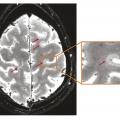

La sclérose en plaques (SEP) est une maladie neuro-inflammatoire chronique du système nerveux central (SNC). Elle est caractérisée par la présence de lésions (ou plaques) au niveau du cerveau et/ou de la moelle épinière et/ou des nerfs optiques. Au sein de ces lésions inflammatoires, la gaine de myéline entourant les axones des…

La sclérose en plaques (SEP) est une maladie inflammatoire et dégénérative du système nerveux central qui concerne environ 120 000 personnes en France. Elle débute habituellement chez l’adulte jeune, en moyenne vers 30 ans, mais peut apparaître à des âges plus extrêmes, rendant l’évocation du diagnostic plus difficile et,…

En dépit de mécanismes auto-immuns incontestés impliqués dans la physiopathologie de la maladie, la sclérose en plaques est de plus en plus considérée comme une pathologie neurodégénérative. Sur le plan clinique, la composante auto-immune se traduit par la survenue de poussées. Sur le plan paraclinique, il s’agit de l’apparition de…